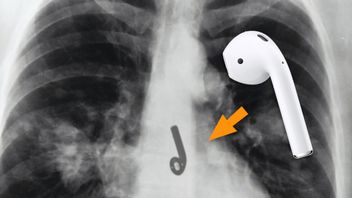

Amerykanin połknął słuchawkę Apple AirPods podczas snu

Pewien mężczyzna odczuwał dyskomfort podczas picia wody i ucisk w klatce piersiowej. Czyżby objawy koronawirusa? Otóż nie, prześwietlenie pokazało, że w jego przełyku tkwi słuchawka AirPods, połknięta podczas snu.

Tech

Arkadiusz Strzała

8 lutego 2021 13:24